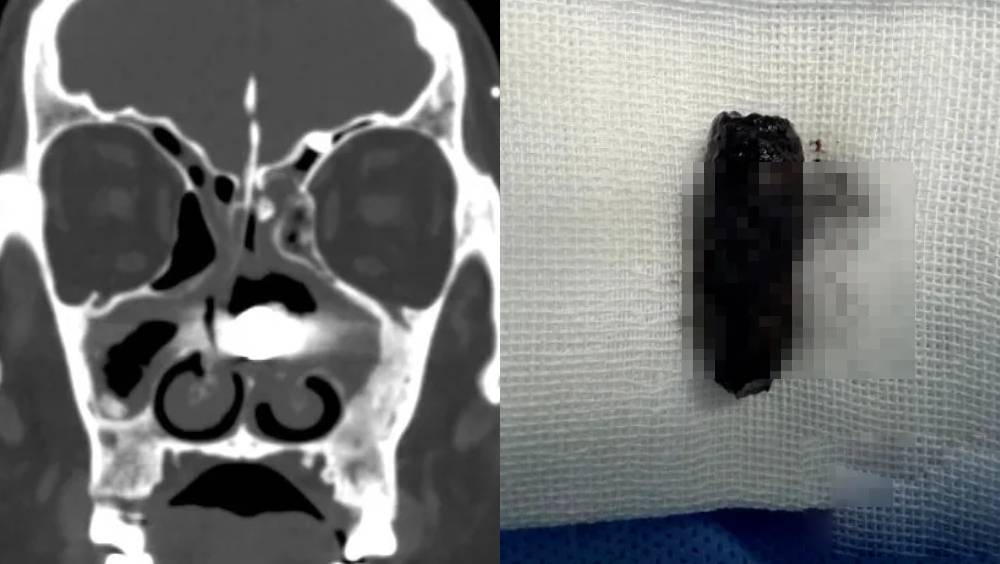

湖北五旬男鼻流膿傳異味多月不癒 驚揭螺絲「藏」鼻腔40年

湖北十堰市一名五旬男子,近3個月飽受鼻腔流膿、伴隨強烈異味困擾,求醫後驚訝地發現,病源竟是一枚已在其鼻腔內「藏身」長達40年的螺絲釘。醫生憑藉精湛手術,最終成功將這枚「計時炸彈」取出,為病人解除長年隱患。 相關新聞:成人用品「意外」滑入肛門 深圳男拒即時處理3日後腸道穿孔 58歲的林先生因鼻子持續流膿發出異味,於3月7日前往十堰市太和醫院耳鼻咽喉頭頸外科求診。接診醫生蔡正敏在問診時,敏銳地察覺到其